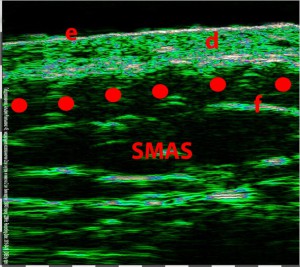

-Lifting με νήματα

-Μέθοδοι θεραπείας υψηλής ενέργειας

(λέιζερ, RF-Ραδιοσυχνότητα, HIFU-Υψηλής Έντασης Εστιασμένος Υπέρηχος, κ.λπ.)